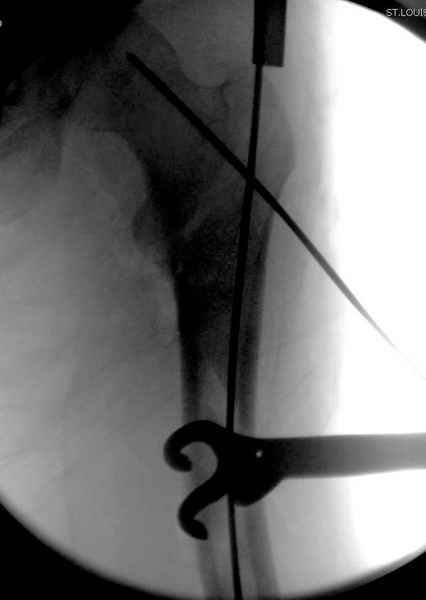

Как раз недавно у меня был примерный случай: больному 36 лет, поступил ночью, травма в результате мотоциклетной аварии, кроме чрезвертельного и спирального перелома левого бедра имеется переломы костей предплечья с этой же стороны. Скелетное вытяжение, а на следующий день больной про оперирован на ортопедическом столе с дистракцией. Чтобы не расколоть чрезвертельный перелом провели временную спицу ближе к переднему кортексу, из малого разреза костодержатель для репозиции, а фиксацию провели антиградным штифтом. Этапы операции на снимках.

Да, сейчас это и у нас самый напрашивающийся выбор. Сделали гвоздем ChM, картинки в приложении.